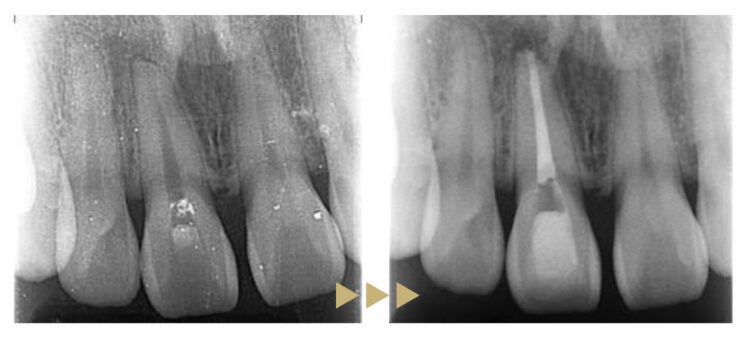

右上前歯は歯の神経が死んでしまったことによる変色がありました。また左上前歯との間に隙間がありました。

治療後の状態

右上前歯を根管治療後、セラミッククラウンにて補綴、左上前歯をダイレクトボンディングで修復し、スペースを閉鎖しました。